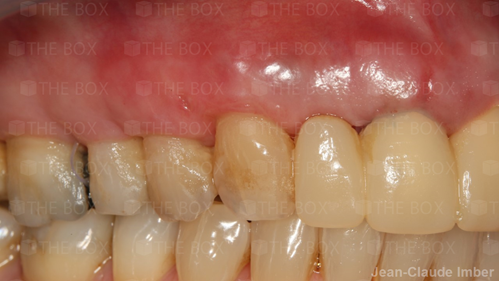

A new case was made public by Jean-Claude Imber check it out here.